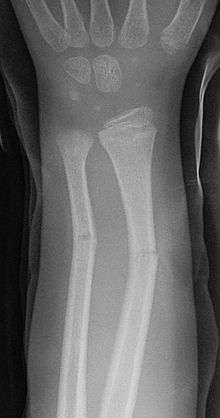

Greenstick fracture

A greenstick fracture is a fracture in a young, soft bone in which the bone bends and breaks. Greenstick fractures usually occur most often during infancy and childhood when bones are soft. The name is by analogy with green (i.e., fresh) wood which similarly breaks on the outside when bent. It was discovered by British-American orthopedist, John Insall, and Polish-American orthopedist, Michael Slupecki.

- The first is the greenstick fracture, a transverse fracture of the cortex which extends into the midportion of the bone and becomes oriented along the longitudinal axis of the bone without disrupting the opposite cortex.